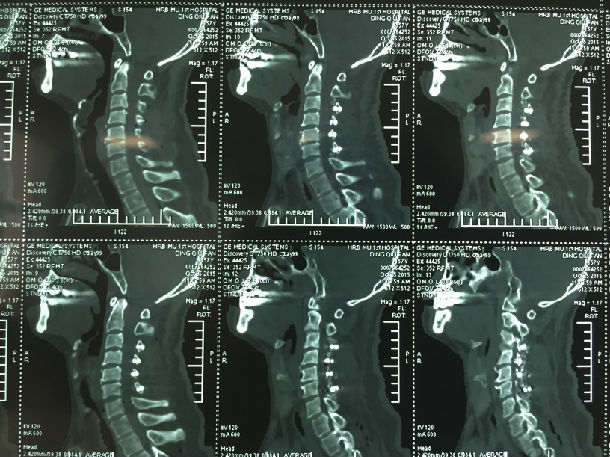

手术前-多节段颈椎间盘突出/黄韧带肥厚/颈椎管狭窄-脊髓损伤

显微镜下经颈后路行单开门椎管扩大成形术-颈椎管明显增宽/脊髓受压解除/患者逐渐康复